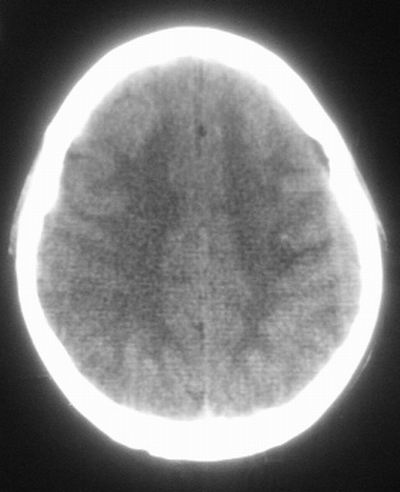

治疗三天后复查ct片示:

治疗三天后复查ct:除左侧额顶叶血肿外。左侧额叶另见片状低密度灶,密度不均匀,境界不清;考虑脑梗塞。

左侧额顶叶血肿伴出血后梗塞!

低密度区应该不是梗塞而是水肿区,建议进一步检查排除占位